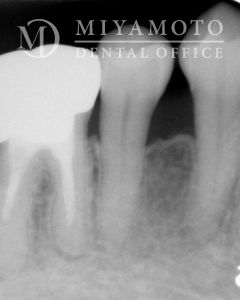

症例14

リグロス®を用いた歯周組織再生療法

1. 治療前

2. 治療後